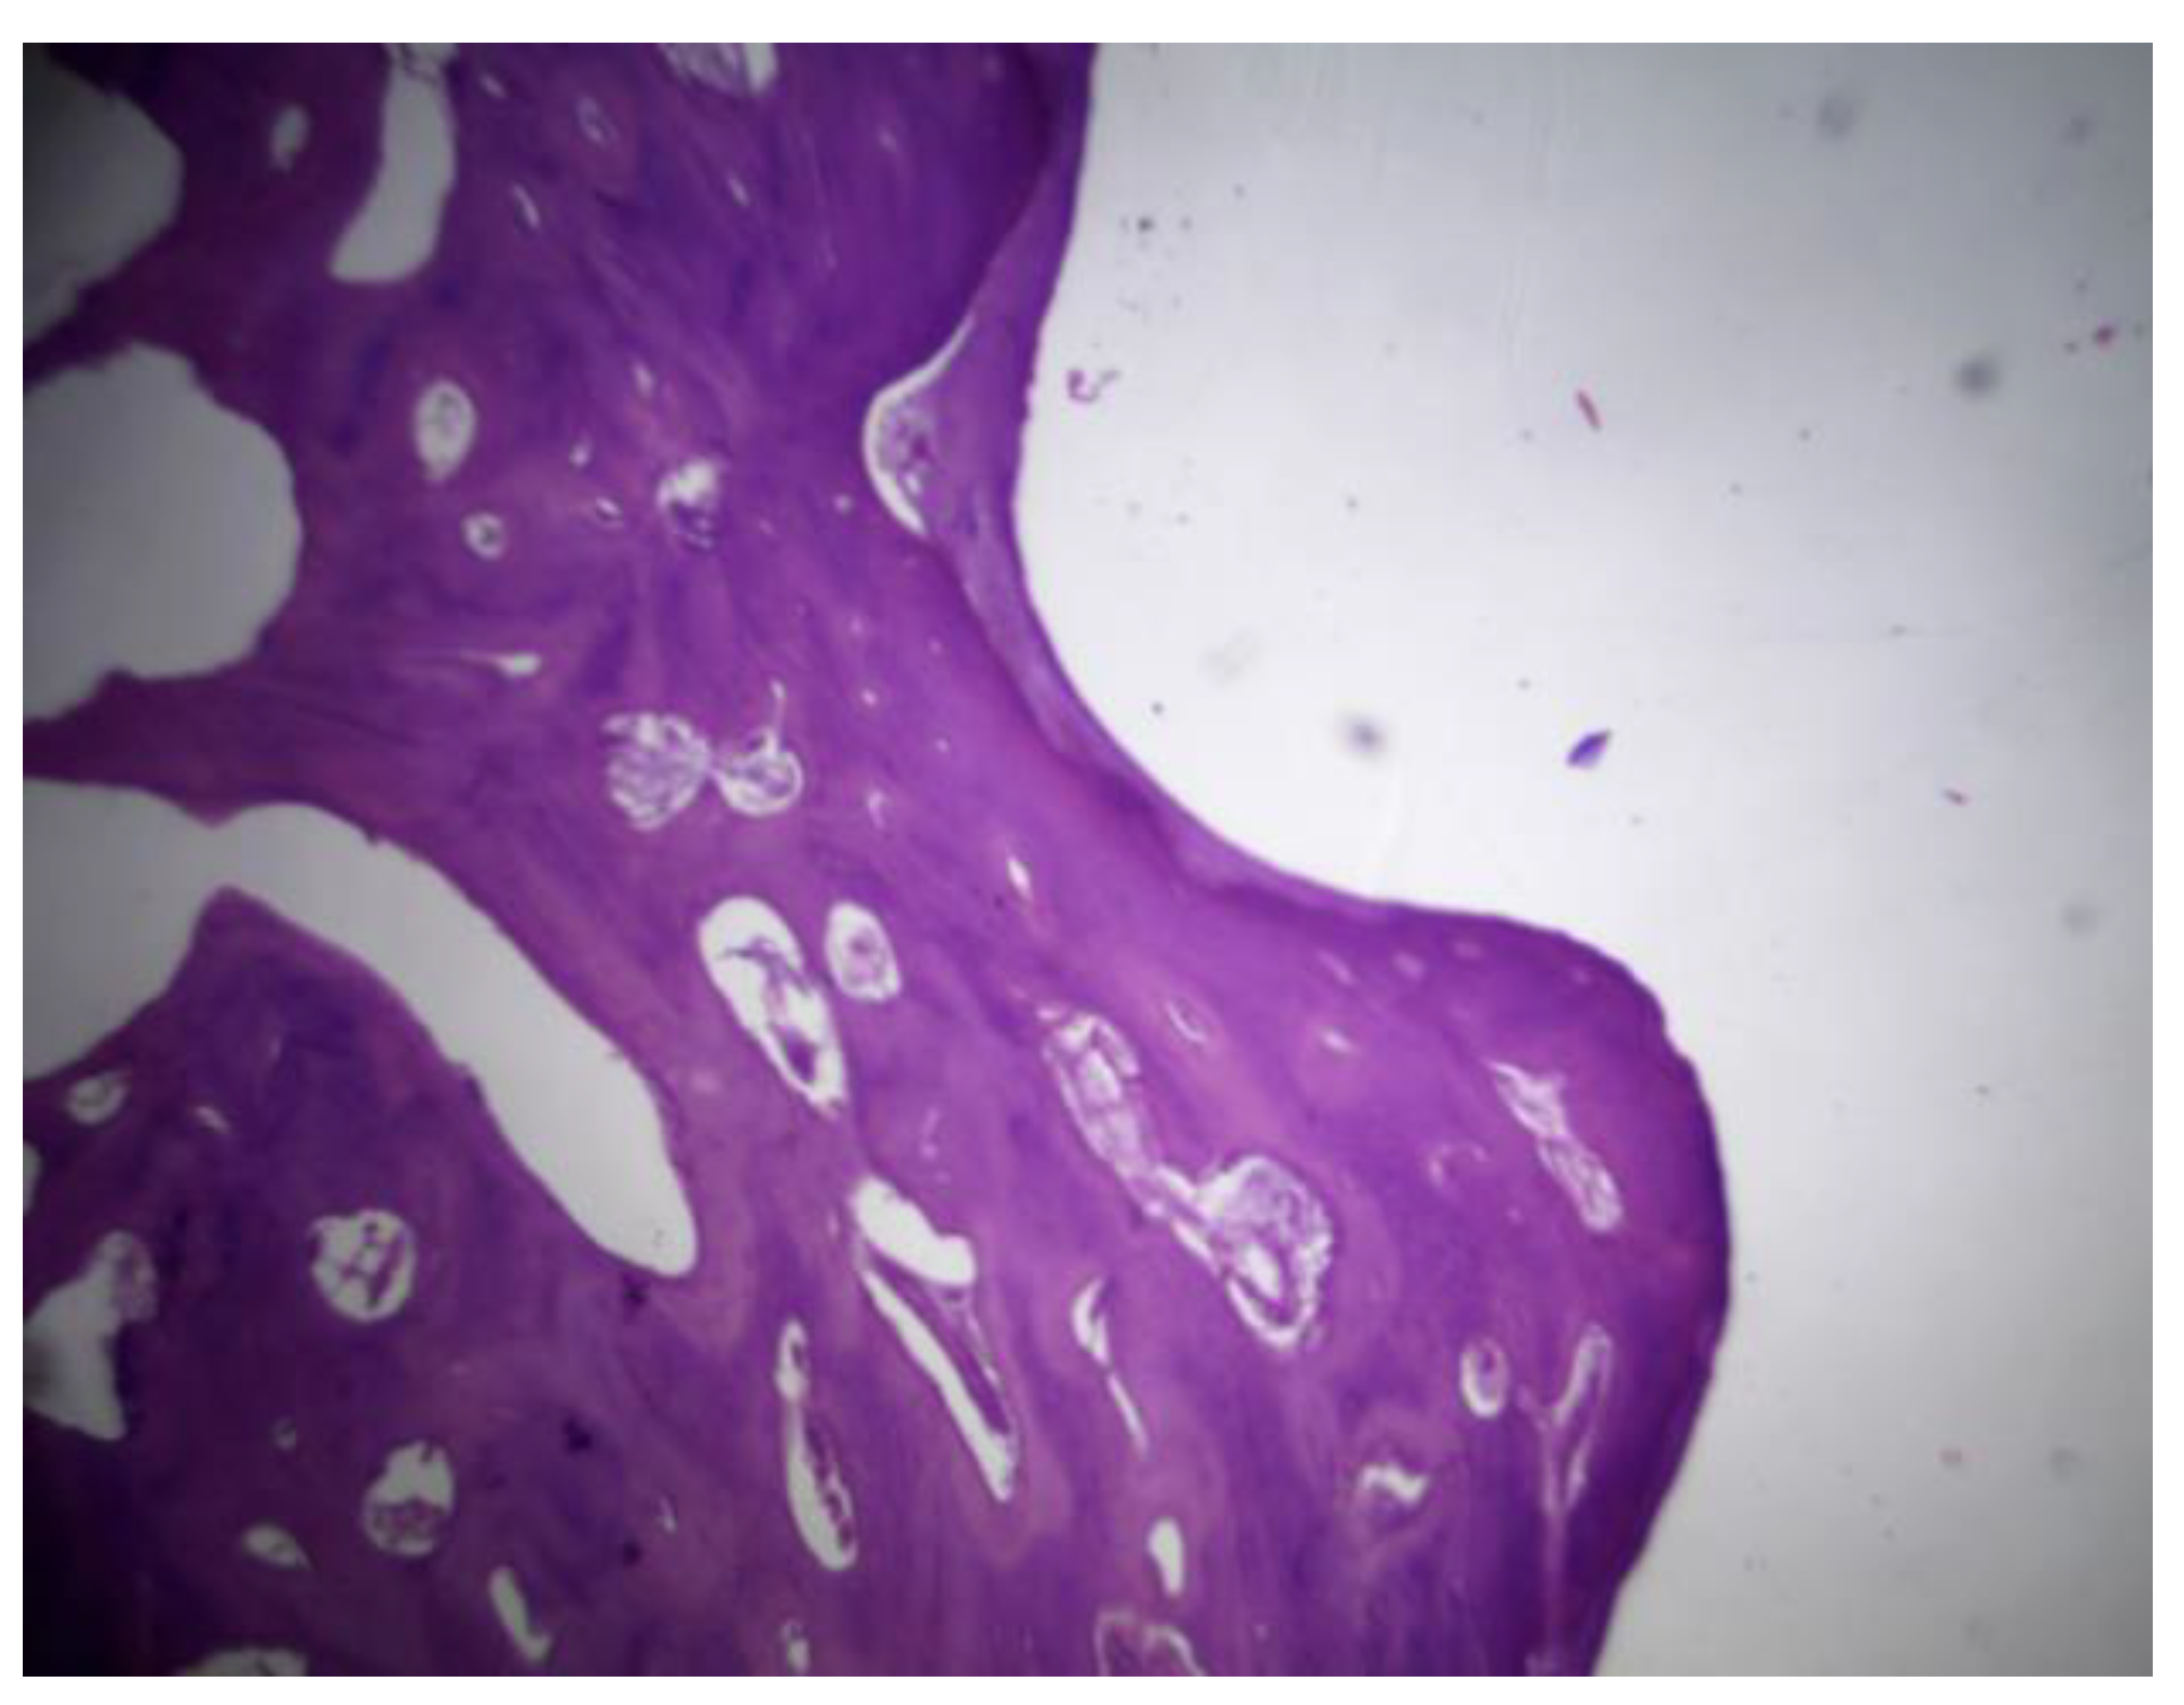

PLDLLA: Histological post-implantation analysis at both the third and fourth months revealed cortical bone in close apposition to the prosthesis, accompanied by mature periprosthetic fibrosis. Effective osteointegration was evident, indicating that the material achieved direct bone contact without the interposition of fibrous tissue a key indicator of stable mechanical and biological integration. The periprosthetic fibrosis and inflammatory response were both mild, with minimal cellular infiltration, reflecting excellent biocompatibility. Scattered neovascularisation was present, supporting ongoing tissue remodelling. Importantly, there were no signs of synovial metaplasia or osteoid formation, further confirming the absence of pathological tissue reactions. Overall, these findings support a stable and successful osseous integration of the PLDLLA implant. (Figure 33)

Figure 33. PLDLLA histological analysis shows cortical bone in close apposition to the prosthesis, accompanied by mature periprosthetic fibrosis.